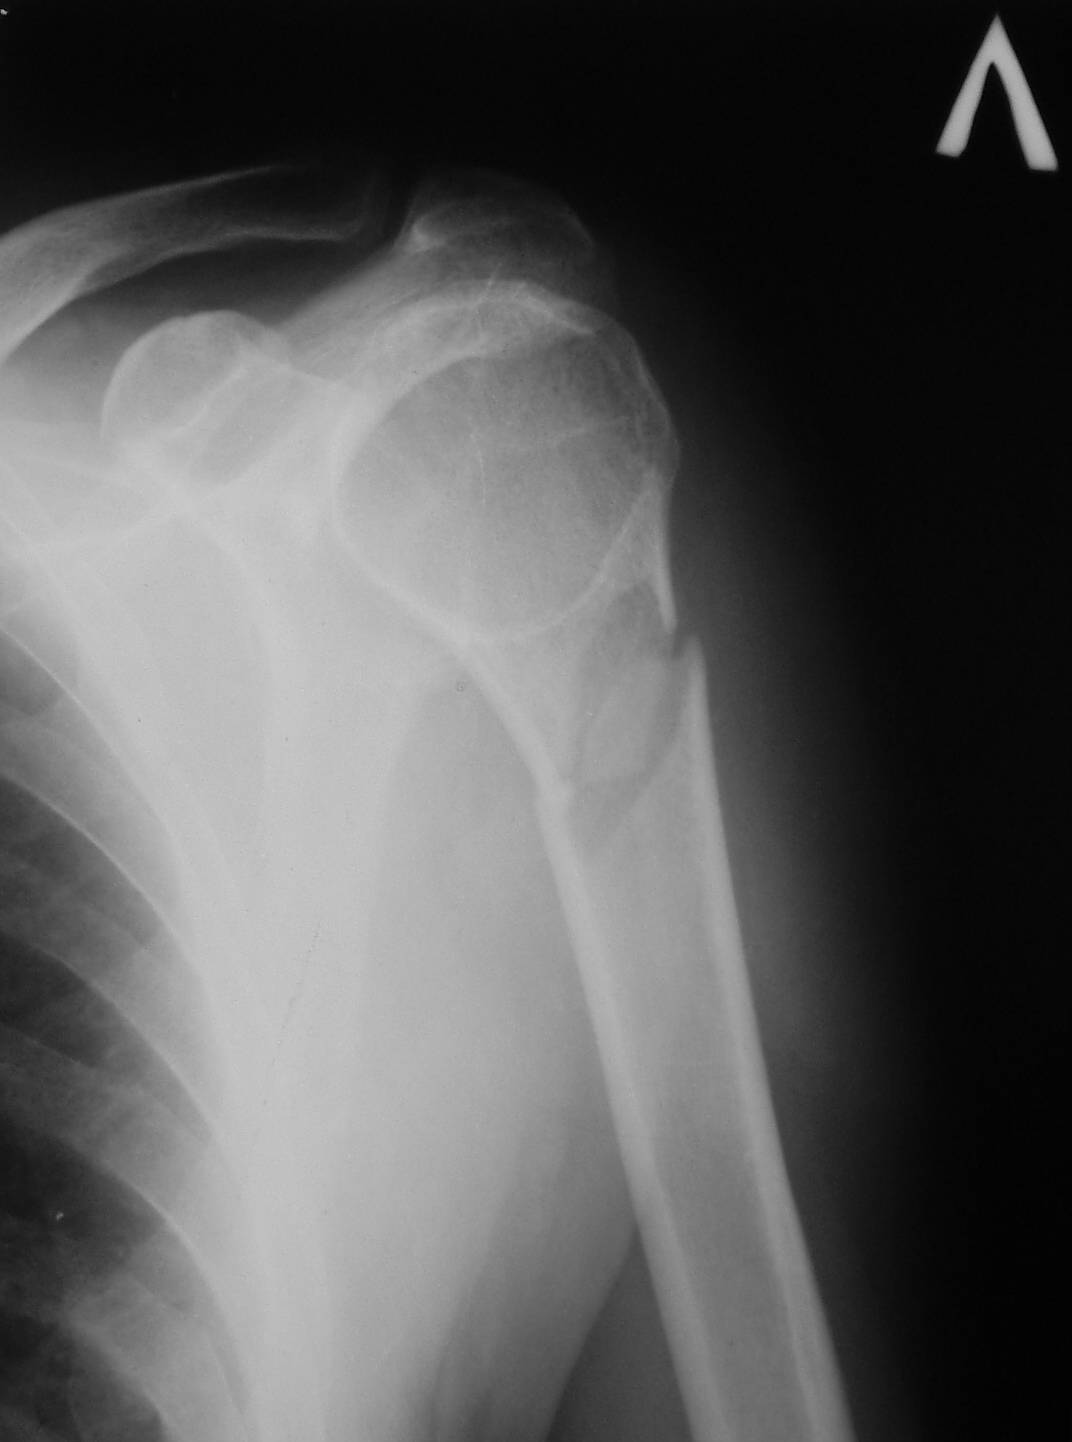

И второй снимок

Противоположный сустав.JPG

Снимок выглядит нормальным. Обратите внимание, в каком положении он сделан.

Если во внутренней ротации - то это совершенно нормальная картина.

Сделайте снимок здорового плечевого сустава в прямой проекции но с максимальной наружной ротацией или внутренней ротацией плеча и увидите в головке такую же "шарополость" с костной структурой ничем не похожую на аневризмальную кисту.

С уважением, А.Семенистый.

Я согласен с уважаемыми А.Семенистым и Л.Лапидус,на мой взгляд проблема в рентгенукладке,у нас ретгенлаборанты тоже частенько грешат,особено по ночам -выдают такие "аневризмальные" кисты.

Подозрение о "шаровидной полости" в головке - это из-за укладки, и на представленном снимке подтверждение правильности рекомендации коллег.